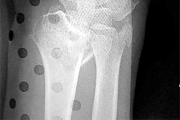

Question 13:

A 6-year-old boy sustains a severe extension-type supracondylar humerus fracture after a fall. Radiographs classify it as a Gartland Type III. The distal fragment is severely displaced posteromedially relative to the proximal shaft. Based on this specific displacement pattern, which of the following nerve structures is at greatest risk of tethering or injury from the proximal fragment?

Correct Answer: Radial nerve

Explanation:

In an extension-type supracondylar humerus fracture, the displacement of the distal fragment dictates the direction of the proximal spike. If the distal fragment is displaced posteromedially, the sharp proximal fragment is thrust anterolaterally, placing the radial nerve at the highest risk of injury. Conversely, if the distal fragment displaces posterolaterally, the proximal spike goes anteromedially, placing the median nerve (and AIN) at greatest risk.